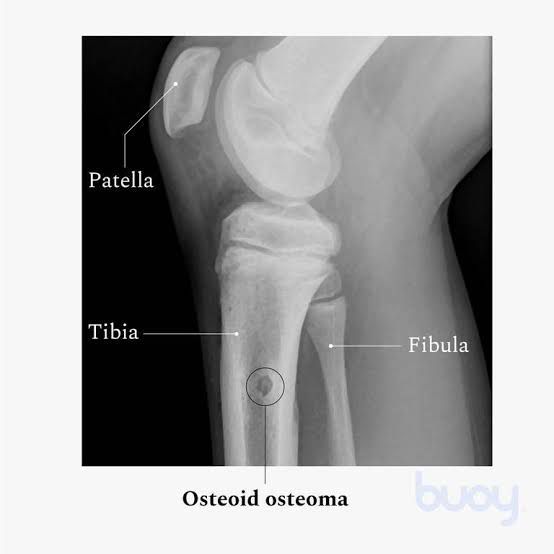

Researchers don’t know the exact cause of an osteoid osteoma. Causes of this benign bone tumor may include: Abnormal growth of cells in your body (neoplasia). Inflammation in your bone. Injury (trauma) to the area where the tumor occurs.